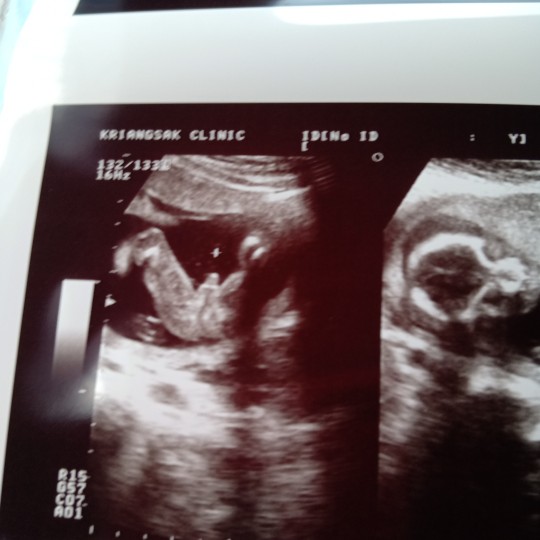

ดีใจมากค้า ได้ลูกชายสมใจ. ขอดูรูปซาวแม่ทีมกันยาหน่อยค้าาาา ได้ลูกชายรึลูกสาวกันน้อ บ้านนี้คนแรกได้ลูกสาวแล้วคนสองหมอบอกลูกชาย ดีใจม้ากกกกกกก